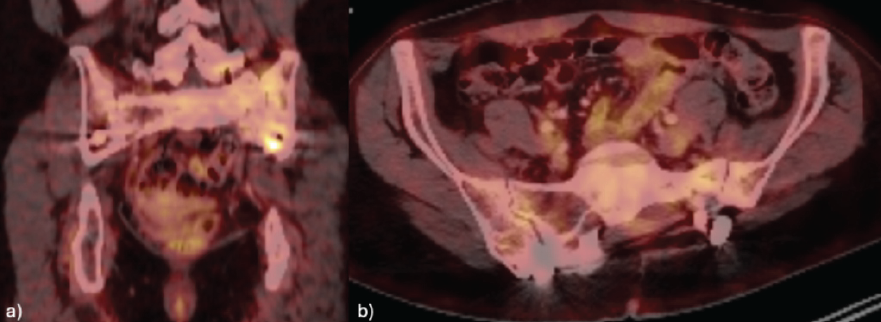

Five-years post-operatively, the patient maintains an adequate clinical follow-up without pain or functional deterioration. Imaging follow-up indicates stability of the lumbopelvic osteosynthesis, without relevant structural complications. SPECT-CT shows no signs of tumor recurrence (Fig. 6).

Figure 6: Single photon emission computed tomography at 5-year follow-up after tumor resection: No evidence of local recurrence on coronal (a) and axial (b) pelvic views.